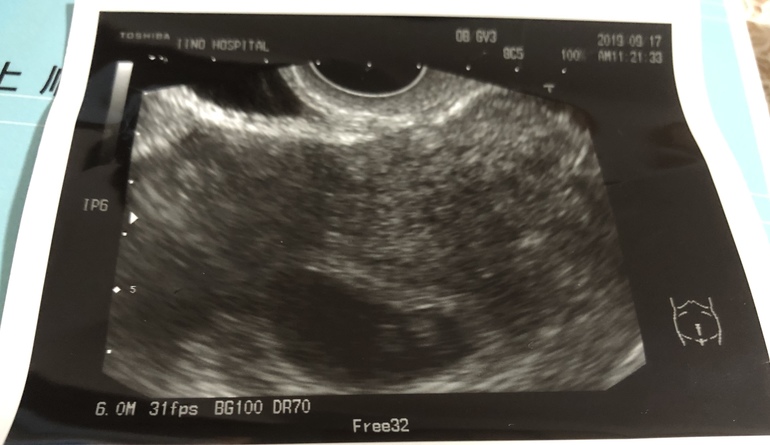

Узи в 7 недель ровно.

Сегодня по М 7 недель ровно. Была у врача на контрольном узи( у нас каждый приём делают узи , по -другому не смотрят).Размер плодного яйца не сказали, ктр вроде 4,9 мм. ( тоже врач не стал акцентировать внимание на нем) .Сердцебиение есть. Сказал, с малышом все хорошо , приходите на контрольный приём через две недели.

Фото узи прикладываю